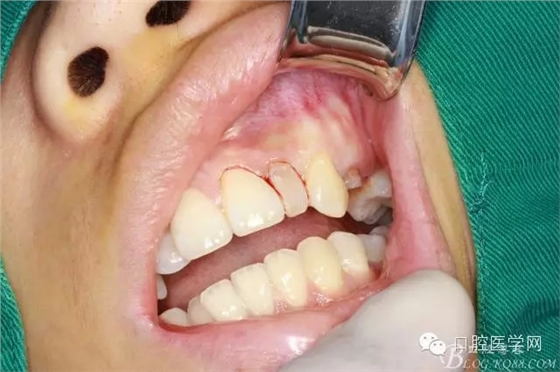

垂直切口

水平切口